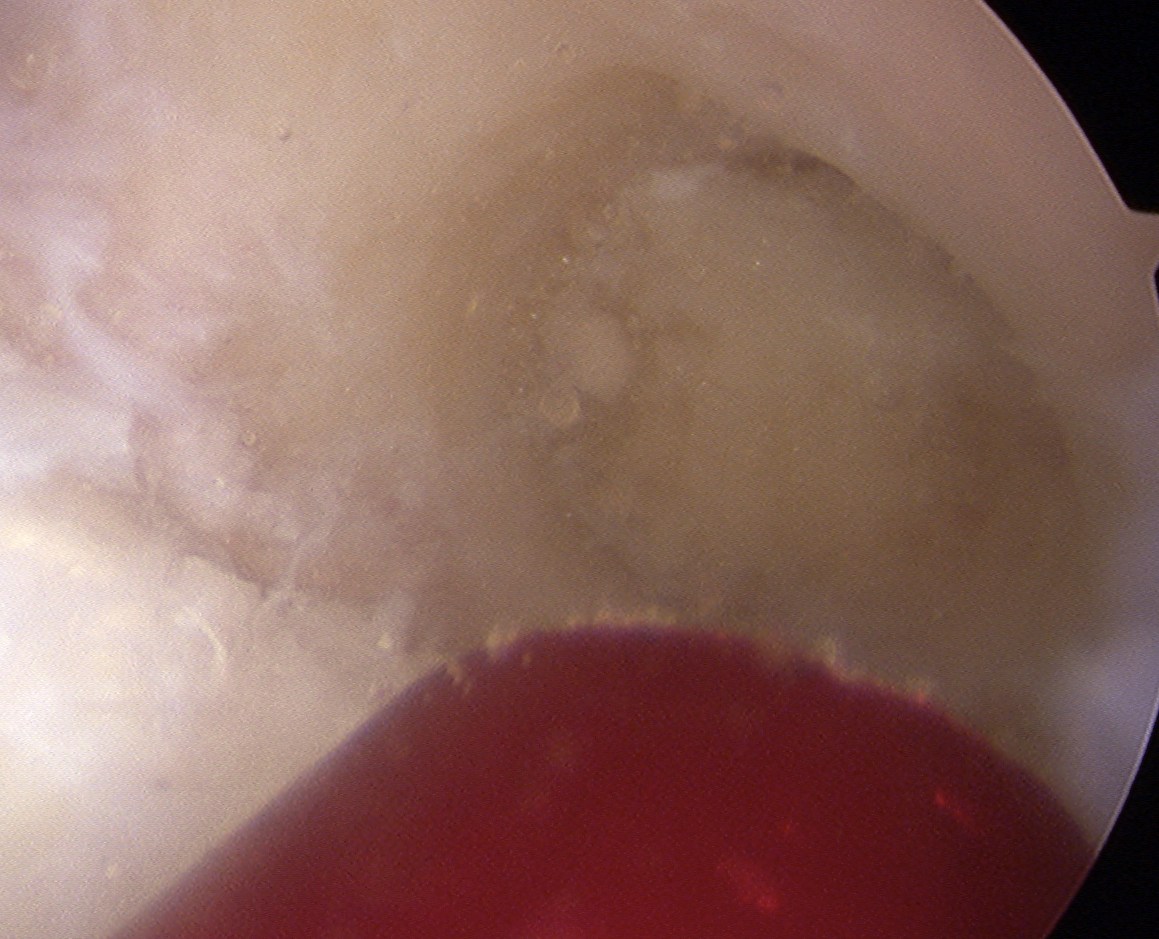

Patient with traumatic failure ACL, previous hamstring with endobutton and bioabsorbable screw

Graft likely too vertical, evidence of tibial tunnel lysis

Tibial bone very poor and screw little bite (advanced very easily too far into tibia, but not seen in joint).

New staple used, but had to be repositioned as cortical bone soft and fracture easily.